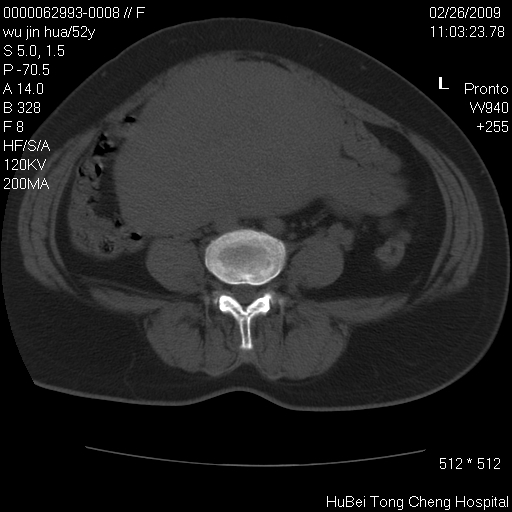

依据平片“腰椎退行性改变”报告,作椎间盘ct扫描时发现:

盆腔彩超报告:子宫肌瘤。(或许也漏诊了!)

影像表现:盆腹腔巨大占位,内密度均匀,边界清,未做强化。

来源:考虑来源于腹膜后肿瘤。

性质:以肉瘤可能性大。